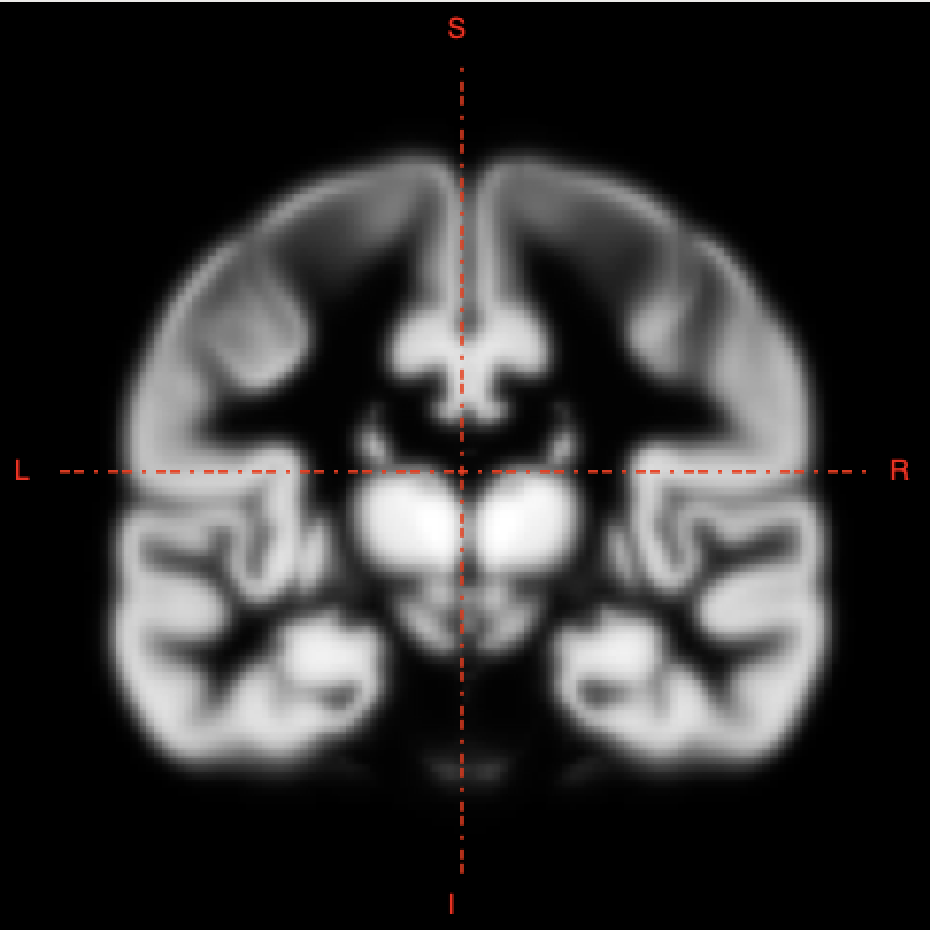

2D slice visualization of the atlas